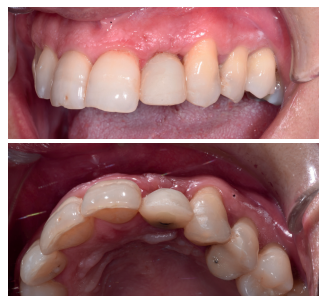

Tras 4 meses de la colocación del implante, habiendo cicatrizado ya el tejido blando después de la segunda fase (Figura 14) se copió el perfil de emergencia, para realizar la restauración fija implantosoportada, mediante una corona cemento-atornillada sobre un pilar de titanio, mostrando un buen aspecto clínico y radiográfico (Figura 15).

En cuanto al análisis de sonrisa, se consiguió también un buen aspecto estético, tal y como se observa en la Figura 16.

En la Figura 17 se puede observar el buen aspecto clínico de la restauración, 6 meses tras la intervención, y la buena aceptación de los tejidos blandos alrededor de la corona, dato que se verifica en la radiografía periapical paralelizada, observando neoformación ósea en las superficies mesial y distal del implante a los 6 meses, en comparación al momento de colocación de la corona (Figura 18).

de la corona en fotografía frontal (arriba) y lateral izquierda (abajo).